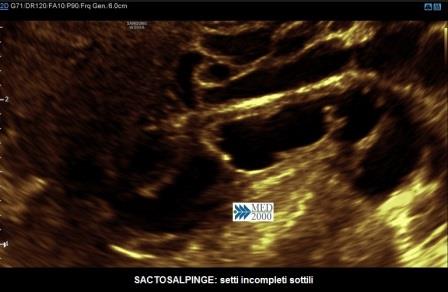

le pareti tubariche, a differenza che nelle forme acute, sono sottili, di diametro < 5 mm.; la salpinge appare dilatata per l'accumulo di liquido e assume una conformazione contorta, ripiegata su se stessa tanto da creare immagini di setti incompleti che, a differenza delle forme acute, sono sottili e di diametro < 5 mm.